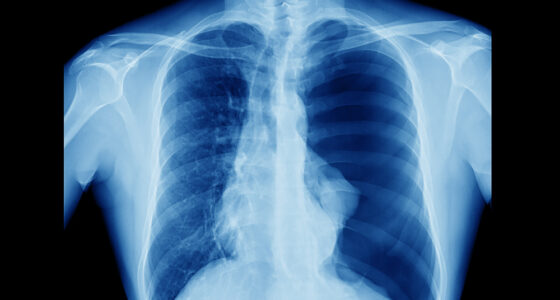

pneumothorax

According to testimony presented during the three-week mesothelioma trial, Salt Lake City, Utah, native Bryce Zundel underwent pleurodesis in 2014 for treatment of a collapsed lung. Pleurodesis can be performed in different ways, but when talc is used, the substance is inserted between the linings of the lung and chest wall to make them stick together. This seals the space and limits further fluid or air buildup. Seven years after his pleurodesis, Mr. Zundel was diagnosed with pleural mesothelioma that his physicians trace back to asbestos contamination of the talc that was used during the surgery.